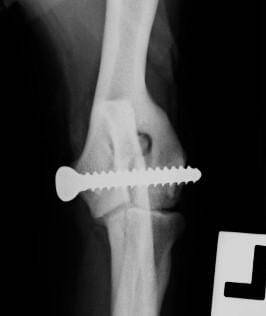

HIFs can be identified via radiography, with lesions most apparent on a craniocaudal projection (Figure 2), but they can be missed if the beam is not parallel with the plane of the fissure. A 15° craniomedial-caudolateral oblique projection has been proposed as the most likely projection to identify a fissure, but it may be prudent to obtain several different oblique projections in a case where there is strong clinical suspicion for the disease. CT or MRI are more sensitive for the identification of fissures and are indicated if available.

HIF is most commonly treated by placing a transcondylar screw across the fissure, but this is associated with a high incidence of post-operative complications. Overall complication rate in one study of 57 dogs (79 elbows) was 59.5 percent, with seroma (25 elbows) and surgical site infection (SSI; 24 elbows) being seen most commonly. At last known follow-up (variable time post-surgery), 34 elbows were subjectively sound and 19 were still showing lameness (Hattersley, 2011). Due to this very high complication rate, mediolateral screw placement has been proposed, but this is more demanding as the safe corridor is smaller in this direction due to the shape of the humeral condyle. There are various techniques to place screws accurately, such as using specialised drill guides and fluoroscopic guidance, but no technique is foolproof!

Larger diameter bone screws are usually placed, in an attempt to limit the risk of fatigue failure of the screw (Figure 3). Use of a shaft screw with a large unthreaded portion and a negative profile thread engaging in the trans-cortex has also been reported, as these screws also offer increased resistance to fatigue failure. However, healing of the fissure has again been reported to be inconsistent.